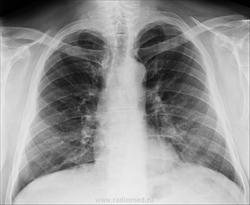

Хр. бронхит это не наше заключение. Есть усиление лёгочного рисунка обоих лёгких. В правом верхние сегмегты, есть очаговые тени слабой интенсивности. Я бы написал пневмонию. Очень характерно для вирусной.

Характерно как для бронхопневмонии, так и для Твс.) Сейчас больного дообследуем по полной!)

Пневмонии не вижу.

Тоже бы написал усиление и обогащение легочного рисунка. И порекомендовал бы R-контроль.

Это просто обогащенный рисунок, суммированный с ребрами. С другой стороны точно такой же.